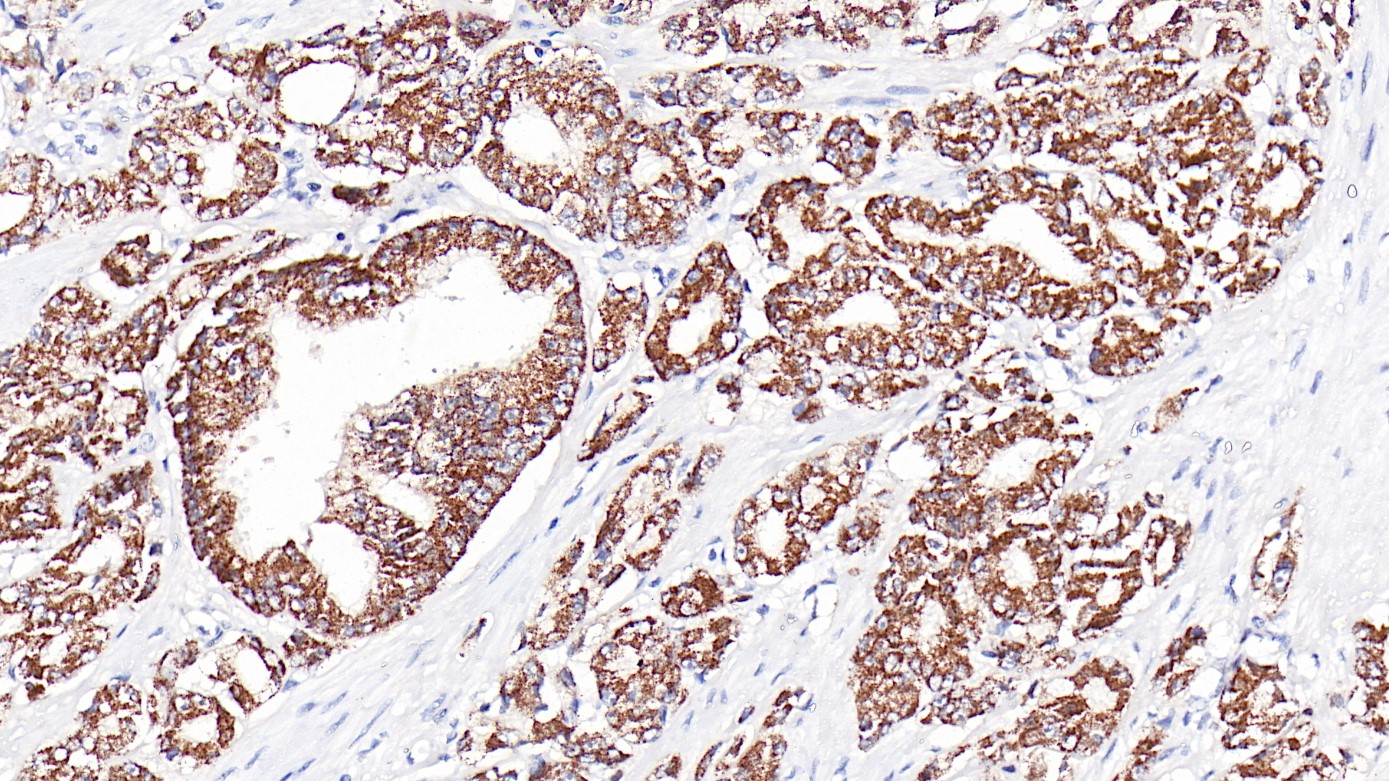

1.Yuanyuan Li,Honggang Li,Liquan Zhou. EZH2-mediated H3K27me3 inhibits ACE2 expression[J]. Biochemical and Biophysical Research Communications,2020,526(4).

2.Unmesh Jadhav,Elisa Manieri,Kodandaramireddy Nalapareddy,Shariq Madha,Shaon Chakrabarti,Kai Wucherpfennig,Megan Barefoot,Ramesh A. Shivdasani. Replicational Dilution of H3K27me3 in Mammalian Cells

and the Role of Poised Promoters[J]. Molecular Cell,2020,78(1).